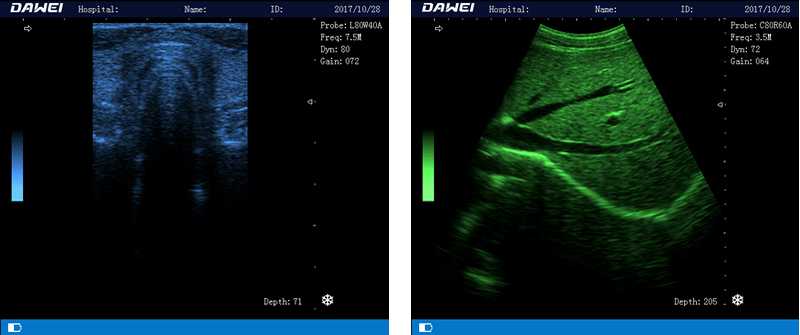

筆記本全數(shù)字超聲診斷儀

1.優(yōu)質(zhì)的數(shù)字成像技術(shù),圖像更清晰